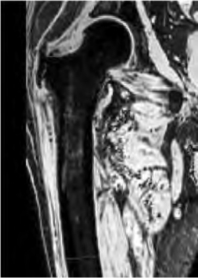

·用磁性套索在另两个正交断面上选定部分断层进行图像分割,光标移到分割边界处单击鼠标左键,绘制一个点,在边界处移动光标,可见磁性套索随光标位置不同吸附不同的边界,选择吸附正确的边界单击鼠标定义下一个点,依此重复沿边界绘制一系列点,绘制完轮廓,双击鼠标左键闭合轮廓线(图3-15),按下Ctrl键可以绘制直线。

图3-15 磁性套索在冠状面绘制轮廓(红色)